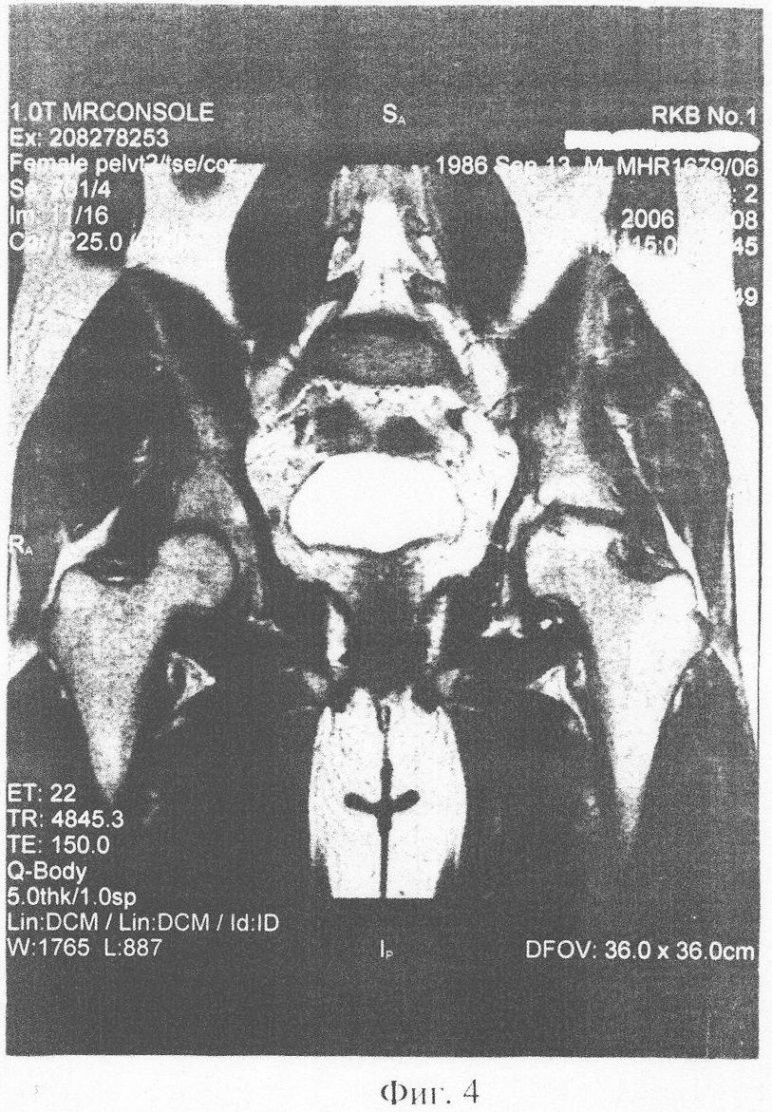

В августе 2005 г. был произведен контроль – ЯМР томография (фиг.2). На снимках отмечается положительная динамика – появление “хрящеподобной” ткани, что является свидетельством активации хондробластов. Клинически – прекратились боли в суставе, появился больший объем движений. Ввиду достигнутого эффекта лечения операция протезирования отменена.